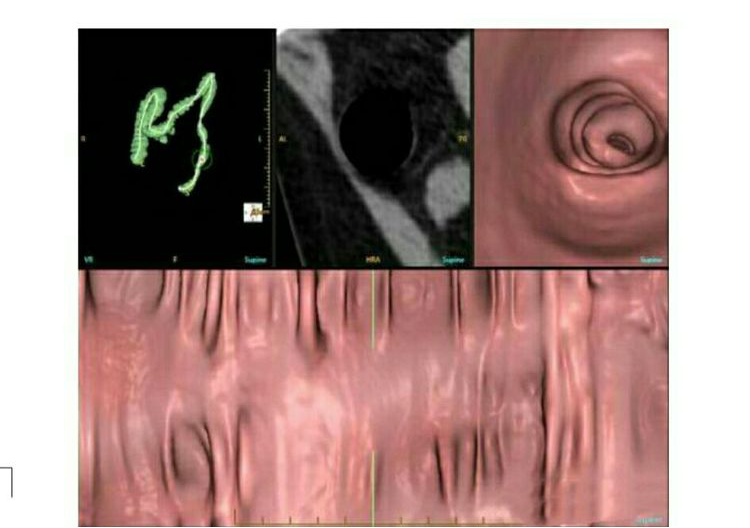

二.消化系统、泌尿系统:

通过128多层螺旋CT 自带多期增强扫描模式,如肝脏三期扫描可以明确诊断肝癌、肝血管瘤等;肾脏、输尿管、膀胱造影可以诊断泌尿系疾病;虚拟结肠镜简单有效的评估结肠,相比方便、达到位置远、腔内腔外都可观察的特点。

1、虚拟结肠镜

简单有效的评估结肠,具有方便等优势